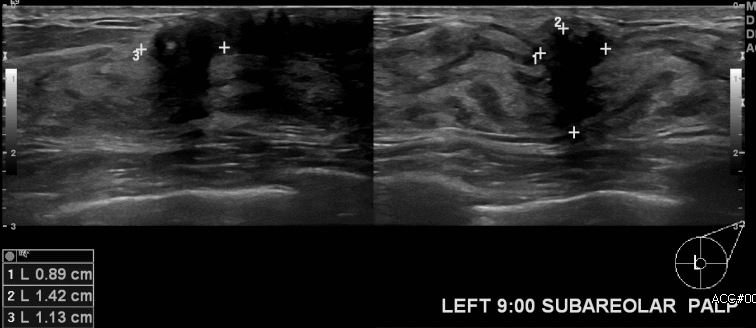

상기환자  우측유방의 결절로 내원하신 50대 여성분으로 타원에서 해마다 건강검진으로

추적해오던 중 좌측 9시 유륜부 근처 새로  만져지는 멍울 조직검사 시행하여 좌측 침윤성소엽암 진단되었습니다.